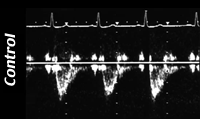

Доплер ЭХО КГ нисходящей аорты до начала процедуры

Доплер ЭХО КГ нисходящей аорты после начала процедуры